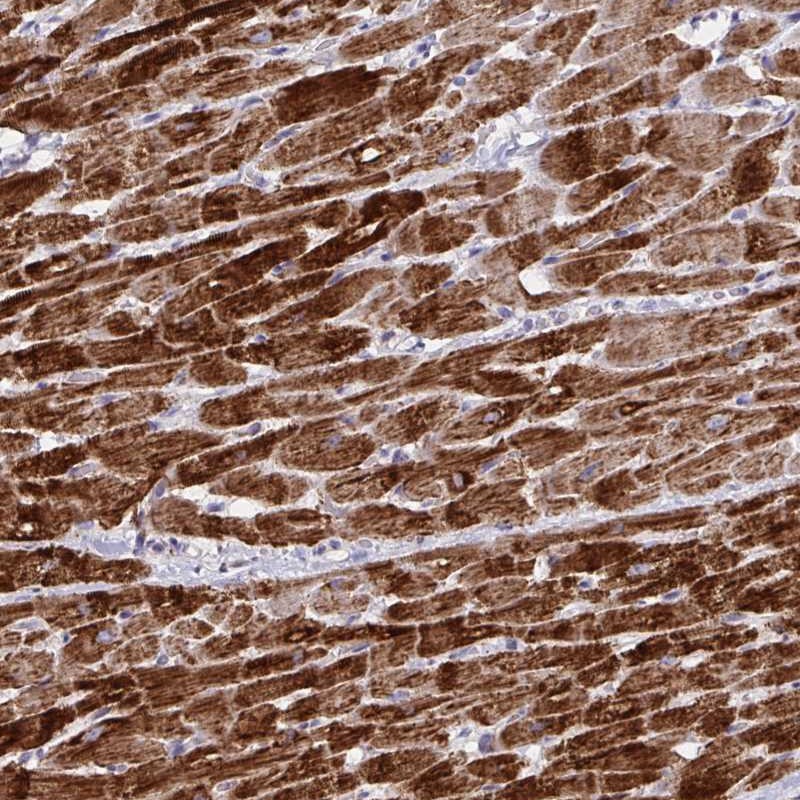

Immunohistochemical staining of human heart muscle shows strong cytoplasmic positivity in myocytes.